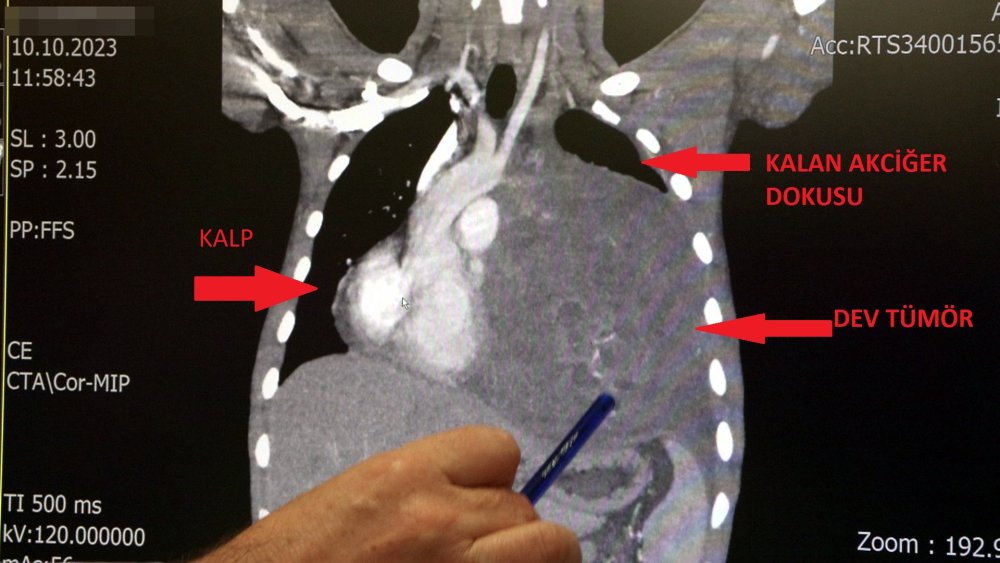

İstanbul'da yaşayan 21 yaşındaki Burak Aktaş, Temmuz ayında işe girmek üzere sağlık raporu almak için hastaneye gitti. Herşey yolundaydı ve raporunu alarak iş başı yaptı. Bir ay geçmeden nefes darlığı, halsizlik, öksürük gibi şikayetlerle başka bir hastaneye gittiğinde ise ilk şoku yaşadı. Sol göğüs boşluğunda portakal büyüklüğünde bir kitle tespit edilmişti. Yapılan biyopside tümörün akciğer kaynaklı olmadığı, henüz cenin aşamasında eşey hücrelerinin farklılaşmasıyla gelişen "immatür teratom" teşhisi kondu. Kitleyi küçültmek için kemoterapi uygulansa da tam tersine tümör 2 ay içinde neredeyse 10 katına çıktı ve büyük bir karpuz boyutuna ulaştı. Sol akciğerinin yüzde seksenini kağıt gibi ezen, kalbini göğüs duvarında 12 santim sağa kaydıran ve hem kalbe hem beyne giden ana damarlara baskı yapan 6.5 kilo ağırlığındaki dev tümör, Koşuyolu Yüksek İhtisas Eğitim ve Araştırma Hastanesi Göğüs ve Kalp Damar Cerrahisi ekiplerinin birlikte girdiği operasyonla başarılı şekilde çıkarıldı. Operasyon sırasında Aktaş'ın kalbi normal yerine çekildi, sol akciğerin üst lobu alındı, ezilen alt lobu ise anestezi ekipleri tarafından pozitif basınçla yeniden şişirildi. Ameliyatı gerçekleştiren ekipten Prof. Dr. Erdal Taşçı, Aktaş'ın göğüs boşluğunun neredeyse tamamını kaplayan 6,5 kiloluk tümörün teratom (eski Yunancada "canavar tümör') türlerinden biri olduğunu ve embriyonik hücrelerden kaynaklandığını kaydetti.

Prof. Dr. Erdal Taşçı, "Bundan 2,5-3 ay öncesine kadar hiçbir problemi olmayan, hayatını normal devam ettiren bir delikanlı Burak. Göğüs ağrısı öksürük ve nefes darlığı şikayetiyle sağlık kuruluşuna başvuruyor. Orada yapılan tetkiklerinde sol göğüs boşluğunda akciğerinden kaynaklanmayan portakal büyüklüğünde bir kitle tespit ediliyor ve immatür teratom tanısı konuyor. 2 ay arayla yapılan tetkiklerinde ve arada cerrahi öncesi küçültme amaçlı kemoterapi almasına rağmen, portakal büyüklüğündeki tümör, irice bir karpuz büyüklüğüne, yaklaşık 6 kilo 300 grama kadar ulaşıyor. Göğüs boşluğunda kemik kafesi içinde olduğu için, itebileceği iki organ var; biri kalp, diğeri de akciğerler. Soldan sağa doğru büyüdüğü için kalbi tamamen göğüs boşluğunun sağ tarafına itmiş ve kalbe giren ve kalpten çıkan bütün büyük damarları da yer değiştirmenin etkisiyle bükülmüş durumdaydı. Bu nedenle vücuduna yeterince kan gitmiyordu. Ağustos ayının başında portakal büyüklüğündeyken kitle Eylül sonuna irice bir kavun, Ekim ayına geldiğimizde ise bir karpuz büyüklüğüne ulaştığı için, kitlenin büyüme hızı bizi acilen ameliyat yapmaya yöneltti. Yaklaşık 8-10 kat hacimsel olarak artmıştı. Sol akciğer tamamen ezilmiş ve kağıt haldeydi, alt lobu anestezi ekibimiz yüksek basınç uygulayarak tekrar şişirdi. Çok fazla vaktimiz yoktu, kitle basısından dolayı yaşamla bağdaşmayacağından dolayı hızlı hareket etmek zorundaydık. Bize geldikten üç gün sonra hemen ameliyata aldık çünkü tümörden ziyade onun yaptığı baskıdan kaynaklı hayati riski vardı" dedi.

Normalde kalbin özellikle alt ucunun göğüs boşluğunda, iman tahtası orta çizgi kabul edilirse, sola bakar şekilde durduğuna dikkat çeken Prof. Dr. Taşçı, sözlerini şöyle sürdürdü: "Ama bu hastada yaklaşık 12-13 s santimlik kalbin alt ucununu yer değiştirmesi ve kalbe giren çıkan bütün damarlar bükülüp kan akımı bozulmuştu. Kalp Damar Cerrahisi ekibi de bizimle beraber ameliyata girdi. Sol akciğerin üst lobu artık geri dönüşümsüz olarak ezildiği için çıkarmak zorunda kaldık. Kalbi tekrar eski pozisyonuna getirdik. Ameliyat sonrası çok çabuk toparladı. Koşuyolu ailesi olarak böyle büyük bir vakanın altından başarıyla çıktığımız için de ayrıca çok gururluyuz. Bundan sonra onkolog arkadaşlarımız hastamızın yaşamına çok olumlu dokunuşlar yapacak. İmmatür teratom genelde embriyojenik çağda gelişim gösteren germ hücrelerinin farklılaşmasıyla büyür. Vücudun herhangi bir yerinde gelişebilir ve içinde saç, diş, kemik artıkları, jölemsi kıvamda maddeler bulundurabilen bir tümör çeşididir. Kombine tedavilerde çok iyi sonuçlar alınıyor. Bu çocuğumuzu ileride güzel bir hayat bekliyor."